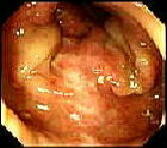

健康な方の腸の内側はきれいなピンク色しているのですが、長期間(数年)に下剤(センナ、アロエ等)を服用し続けますと右図のように、褐色から甚だしい場合には太陽の照らない腸の中なのに日焼けしたごとく「真っ黒」になります。メラニン様色素が腸壁に沈着するために、このような変化が起こります。 緩下剤を中止しますと、約6ヶ月後には、幸いにも元のピンク色に戻ります。

大腸黒皮症ポリ−プはおもしろいことに色素は沈着しません(左)。

中央に小ポリ−プが見られますより高度になると、真黒になり、snake skin (蛇の皮)と称されるほどの色素沈着を来す(右)。